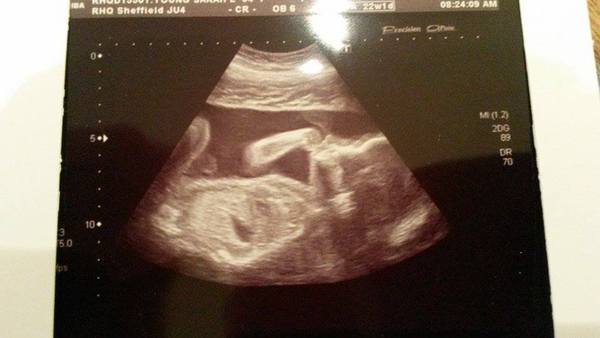

22 weeks, looks like baby is smoking a spliff, haha.

All well.

Gender still a surprise.

Ha ha weebairn brilliant photo and definitely looks like a stoner Wink

Ha! That's brilliant, weebairn!

Haha great photo weebairn, it's so exciting seeing a scan photo :)